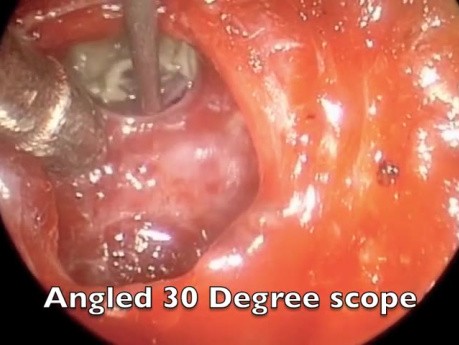

Endoskopowa operacja przysadki - wykorzystanie...

Wideo przedstawia przeznosowy i przezklinowy dostęp do przysadki w celu wykonania operacji siodła. Wykorzystano endoskop kątowy.